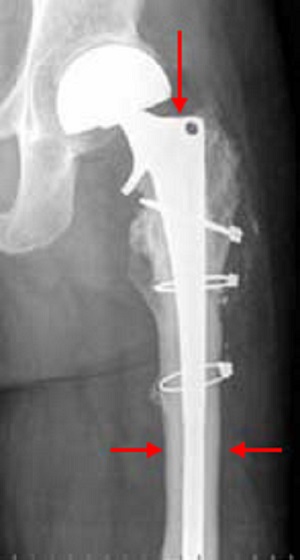

29+ Bone Sarcoma Xray Pics. This is in contrast to most bone cancers that are secondary having developed as a metastasis from another cancer. A bone sarcoma is a primary malignant bone tumour, a type of sarcoma that starts in the bones.

Main types include soft tissue sarcoma and osteosarcoma. It most commonly affects teenagers and young adults with the pelvis, thigh bone and shin bone being the most commonly affected areas. Fibrous dysplasia of bone, microscopic xray. See more of sarcoma and bone cancer research association inc.